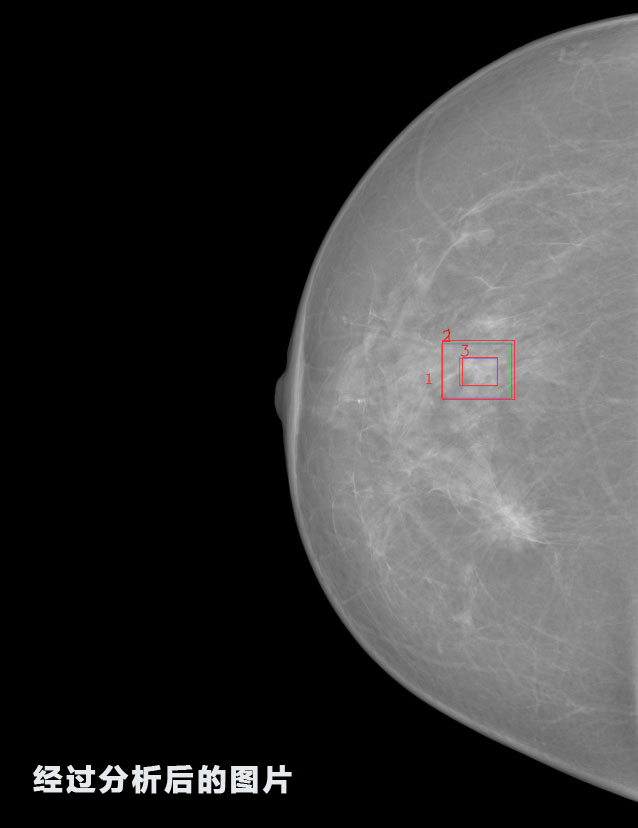

英特健康A(chǔ)I深度學(xué)習(xí)醫(yī)療圖像識別系統(tǒng)案例_乳腺

識別報告:

1.發(fā)現(xiàn)良性鈣化,可能性為19.88%---位置框指數(shù):[1796.0867 1359.8237 2058.1372 1582.5334]

2.發(fā)現(xiàn)惡意鈣化的可能性為15.18%---位置框指數(shù):[1789.4733 1365.9951 2063.7698 1576.0613]

3.發(fā)現(xiàn)惡意鈣化的可能性為12.45%---位于框指數(shù):[1859.3987 1422.3184 2006.5494 1528.2698]